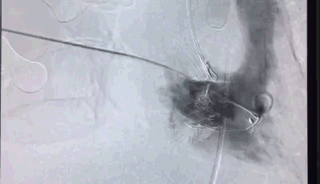

瓣膜植入后右心室造影

王建安教授团队综合该患者CT、超声检查结果,对该患者的情况进行了充分的评估和讨论,最终决定采用LuX-Valve®瓣膜系统对患者进行微创治疗。该手术仅在患者右胸开一个小孔,在心脏不停跳的情况下,通过右心房穿刺,用导管进入心脏内部进行瓣膜置换,瓣膜置换过程耗时20分钟。术后超声和造影显示瓣膜位置良好,无明显反流。手术顺利,恢复良好。